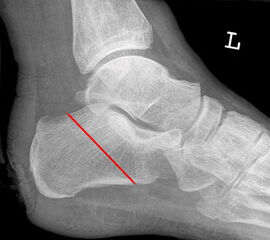

Der kraniale Calcaneus wird so mit der oszillierenden Säge reseziert, dass bei der Fusion mit der Tibia die physiologische Inklination von 30° wieder hergestellt wird (Abb. 48). Wird der Calcaneus zu steil eingestellt, kann das zu erhöhter Druckbelastung am Tuber calcanei und damit zur Ulzeration führen. Eine flache Einstellung des Talus wird von manchen Operateu­ren bevorzugt. Dies ist technisch vielleicht etwas einfacher, führt jedoch zu einer stärkeren Verkürzung. Varus- und Valgusfehlstellungen müssen vermieden werden.

Zur Osteosynthese bevorzugen wir 2-3 kanülierte Großfragmentschrauben (Abb. 49). Postoperativ ist die Extremität für 8 Wochen zu entlasten, wobei zur Sicherheit eine Entlas­tungsorthese verordnet werden kann. Bei schwachen oder unzuverlässigen Patienten empfiehlt es sich, für 8 Wochen einen Ring-Fixateur anzulegen.